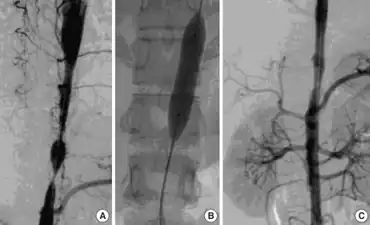

a) 3D-CT angiography- focal stenosis b) percutaneous transluminal angioplasty using balloon catheter c) stent in aorta

Most people with Takayasu’s arteritis respond to steroids such as prednisone. The usual starting dose is approximately 1 milligram per kilogram of body weight per day (for most people, this is approximately 60 milligrams a day). Because of the significant side effects of long-term high-dose prednisone use, the starting dose is tapered over several weeks to a dose which controls symptoms while limiting the side effects of steroids.

Promising results are achieved with mycophenolate and tocilizumab.[14] If treatment is not kept to a high standard, long-term damage or death can occur.

Patients who do not respond to steroids may require revascularization, either via vascular bypass or angioplasty and stenting. Outcomes following revascularization vary depending on the severity of the underlying disease. [15]